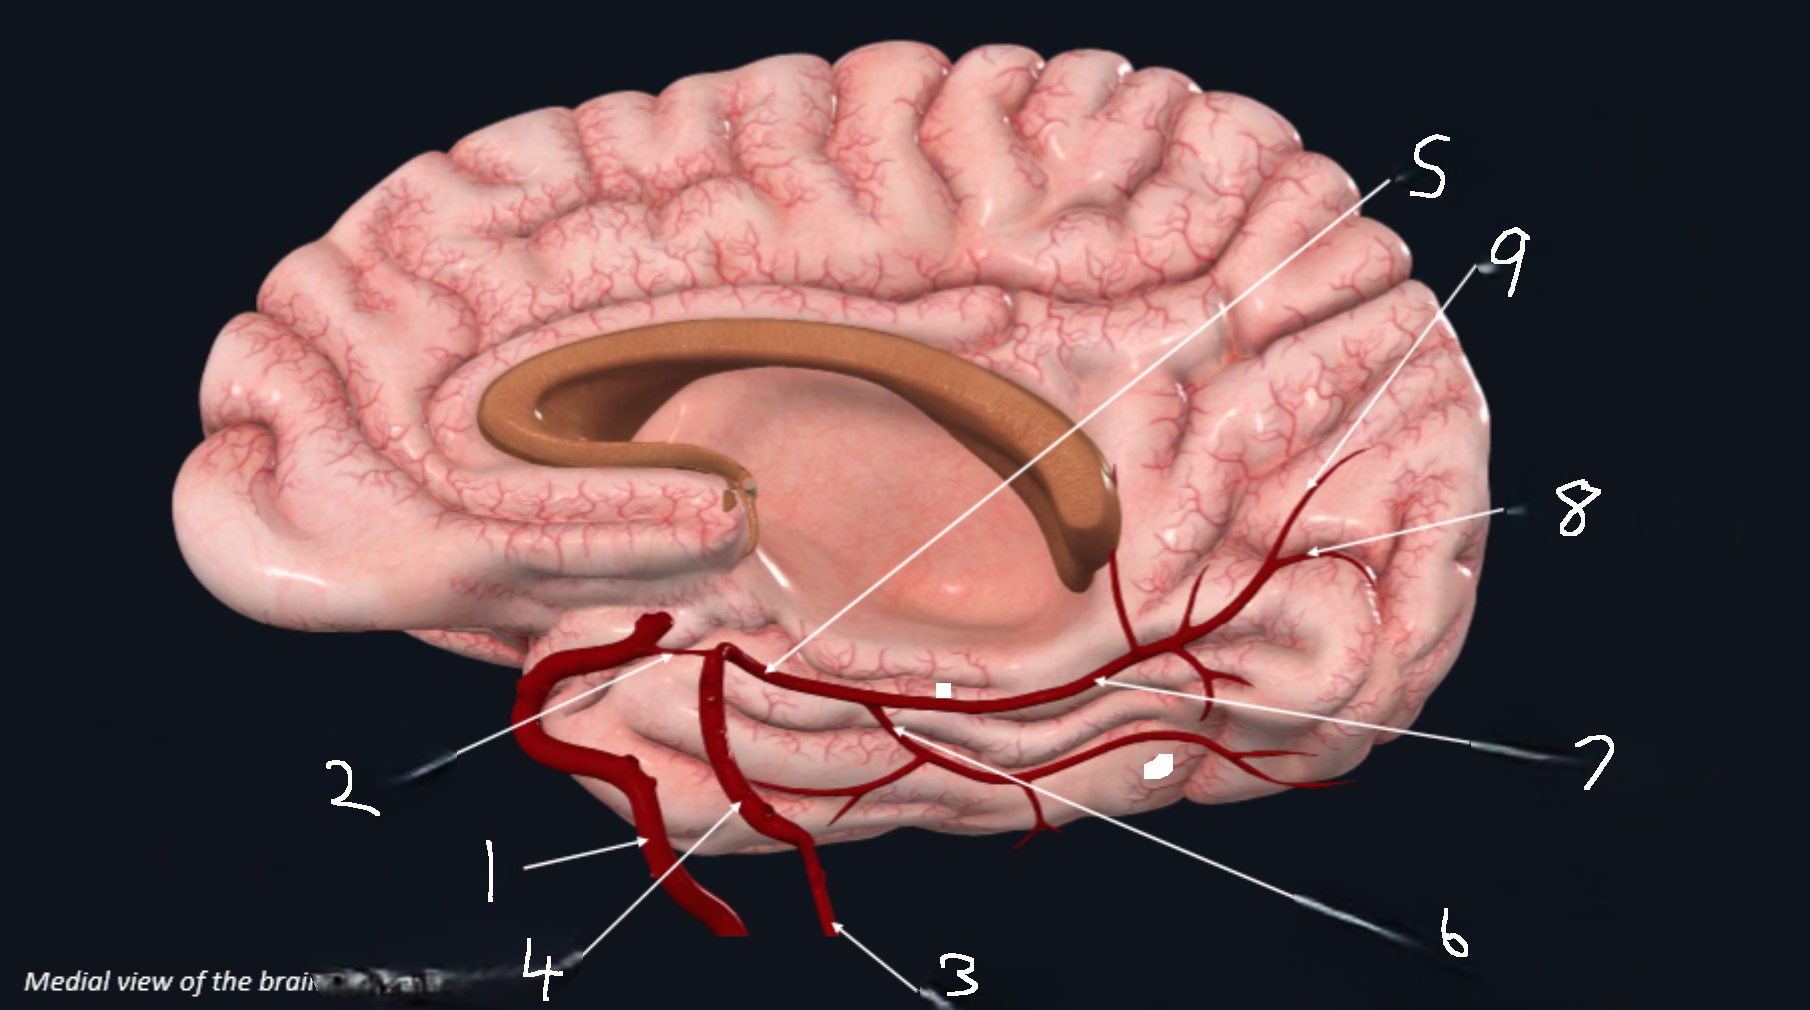

What is 1?

internal carotid artery

What is 2?

posterior communicating artery

What is 3?

vertebral artery

What is 4?

basilar artery

What is 5?

posterior cerebral artery

What is 6?

lateral occipital artery

What is 7?

medial occipital

What is 8?

calcarine branch

What is 9?

parieto-occipital branch